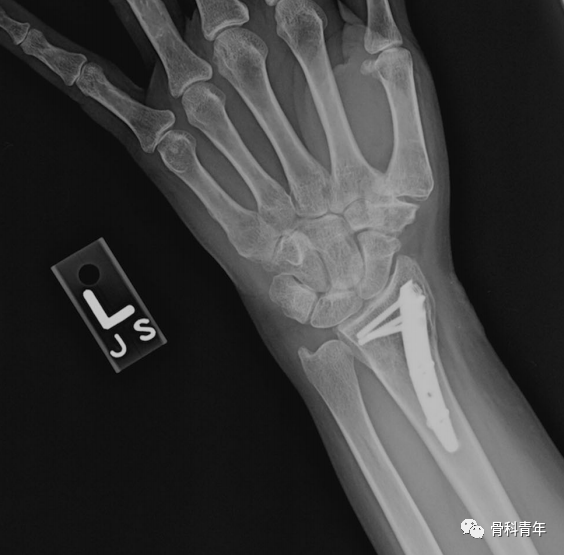

掌侧锁定加压接骨板(Volar locking compression plate,LCP)内固定是桡骨远端骨折治疗的金标准,但LCP并非对所有桡骨远端骨折均适用,如桡骨极远端骨折、背侧缘骨折、掌侧die-punch骨折等;同时,LCP钢板也具有一定的并发症发生率,包括旋前方肌损伤、骨折血运破坏、掌侧软组织激惹、背侧肌腱磨损等,同时对严重骨质疏松患者存在较高的内固定失效风险。